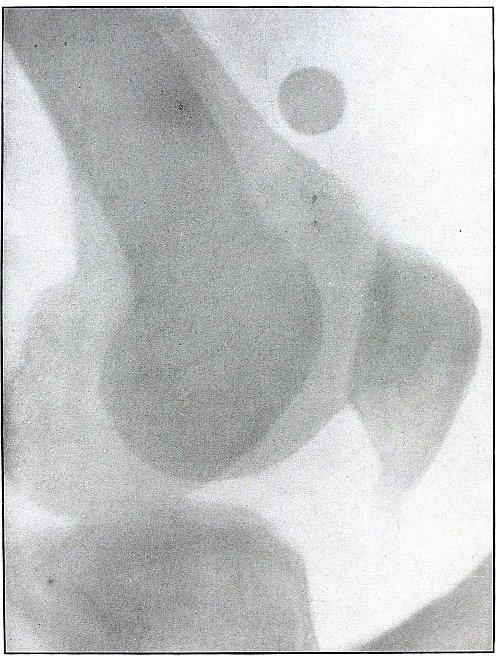

PELVIS.

Rifle—Plate 46.

Gunshot Wound of the Pelvis, with Lodgment of the Missile in the Abdomen.

The course of the bullet was from behind forward, striking the crest of the ilium, on which it was deflected, and spattering off some lead fragments. The slight penetration indicates a velocity of extremely long range and a striking energy lessened by ricochet.

The irregular outline of the shadow of the projectile shows its deformity, and the blurred outline indicates intra-abdominal movement with respiration.

While the missile, as revealed by its shadow, is not a shrapnel ball, the distribution of lead particles is more suggestive of a shrapnel than of a rifle projectile, and the ballistic conditions are more characteristic of the former than of the latter.

There was no abdominal reaction; the invasion of the abdomen was revealed by the radiograph.

The treatment in such cases is noninterference unless subsequent developments furnish definite indications. [Pg 104]